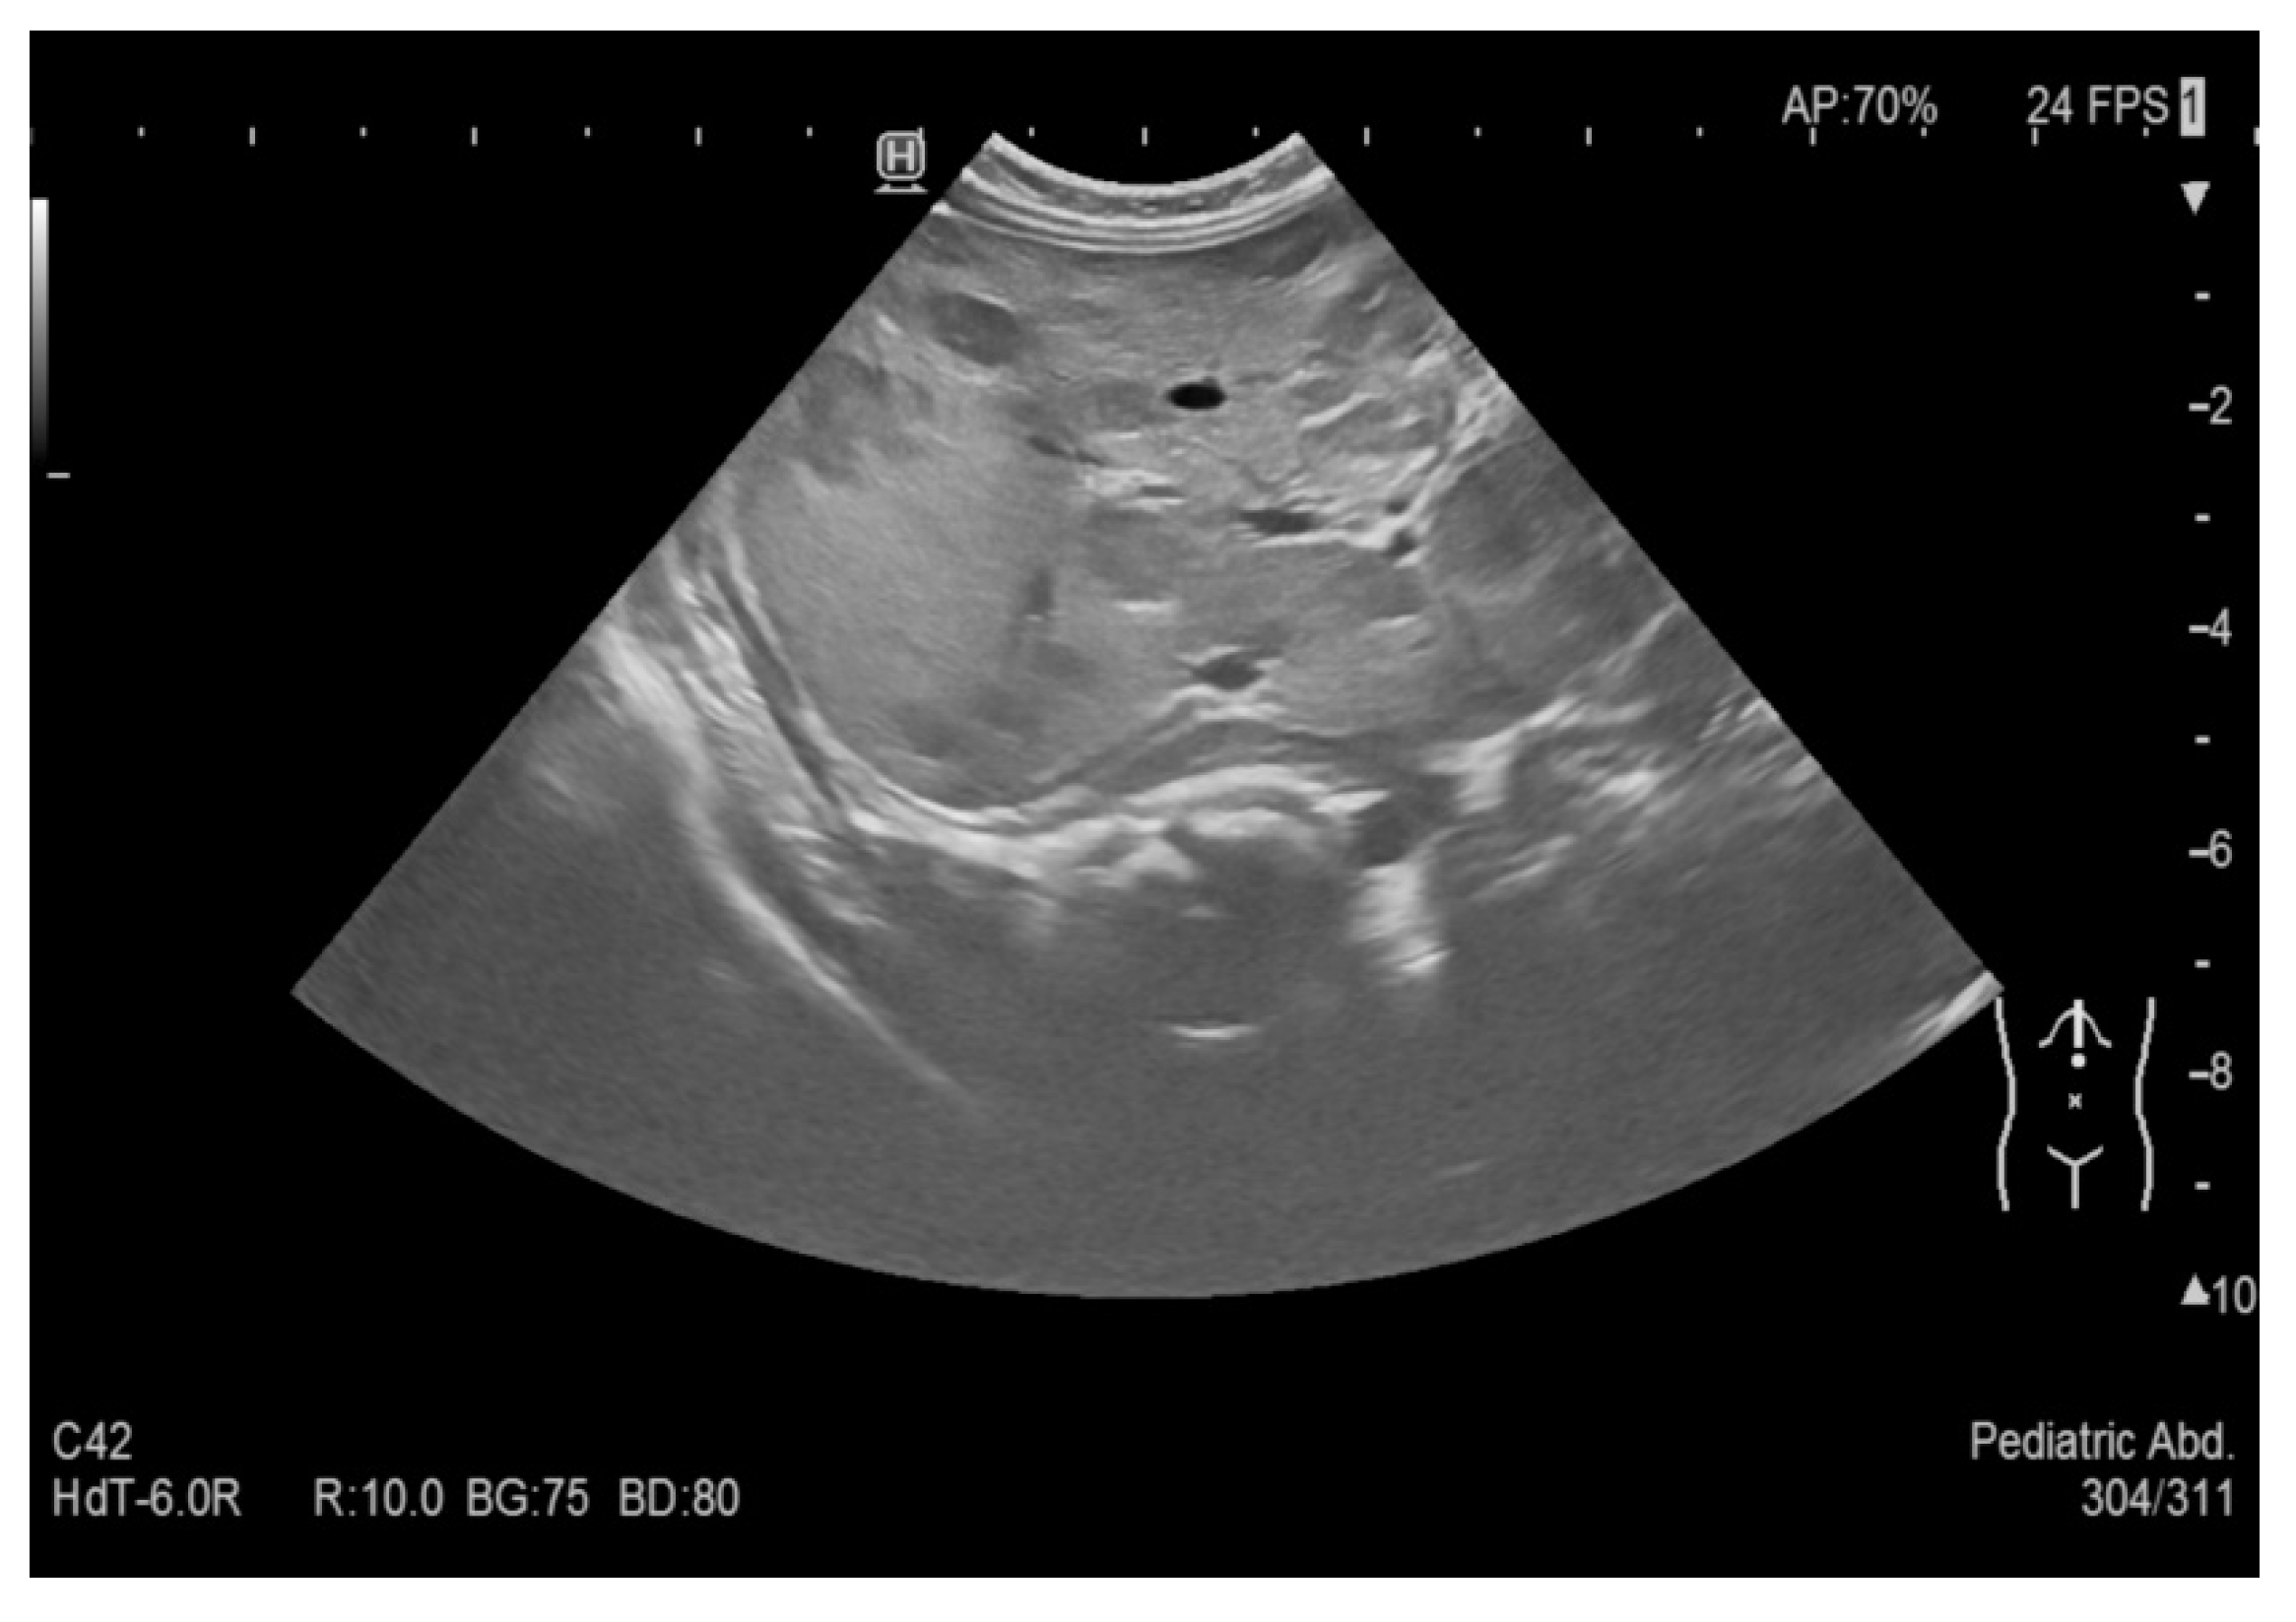

A boy from pregnancy II, delivery I, was born at the 30th week of gestation. The respiratory distress syndrome was identified in history and the neonate was diagnosed and treated at the Neonatal Intensive Care Unit. Cranial ultrasound scan (CrUSS) revealed status post grade II haemorrhage on the right side. A series of ultrasound examinations, performed at bedside at the Neonatal Intensive Care Unit, demonstrated normal images of the abdominal organs (see Figure 1)—the US examination was performed four times on day 3, 17, 24 and 40 of the baby’s life.

Figure 1. Normal image of the abdominal organs.